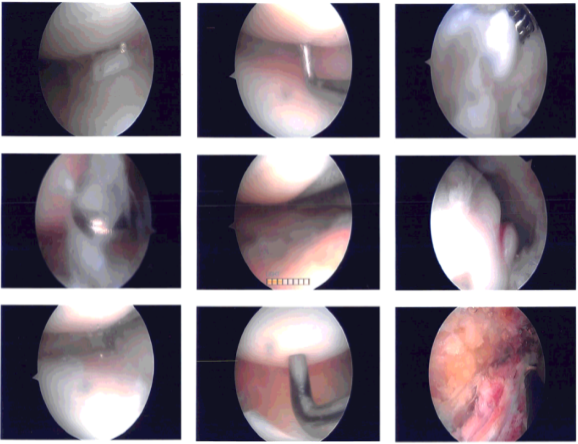

Examination showed intact medial and lateral meniscus as well as intact medial and lateral compartment. There were grade 3 to grade 4 osteoarthritic changes in the trochlea as well as patella. The lateral surface of the patella was denuded cartilage.

There was an osteophyte over the medial femoral condyle which was excised with the use of shaver and burr. Shaver was used to perform chondroplasty. The Coblation wand was also used to perform the chondroplasty. The patellar maltracking could be seen. Decision was taken for lateral release.

Arthroscope was entered through the medial portal and Coblation wand from the lateral portal. Lateral release of the capsule was performed from proximal to distal. All the bleeders were cauterized. Tourniquet was released at the end of the procedure. There was no active bleeding.

Intraoperative photo